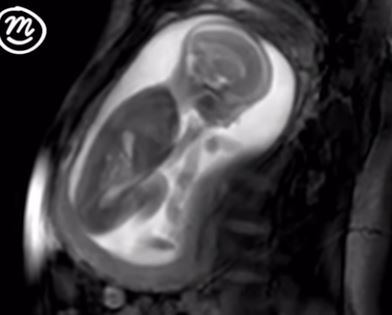

فيديو مدهش لحركات جنين عمره 20 أسبوعا في الرحم.. شاهدوا ماذا يفعل!

نشر موقع "مترو" مقطع فيديو من مشروع "iFIND"، الذي يسمح للآباء والأمهات بمشاهدة حركات الجنين داخل الرحم بعد 20 أسبوعا فقط بفضل التصوير بالرنين المغناطيسي المتطور.

وتعتبر هذه التقنية الموجودة الآن في لندن قفزة رائدة في مجال التكنولوجيا، وتصل تكلفته نحو 10 ملايين جنيه إسترليني، ويُستخدم المجال المغناطيسي لخلق صورة واضحة لرؤية الجنين عند التمدد أو البلع.

نشر الموقع لقطات مذهلة تظهر الجنين، وهو يجذب بلطف الحبل السري ويحرك رأسه، ويخلق تموجات من خلال معدة والدته عن طريق ركلها.

كما يظهر المشروع الجديد حركات بسيطة للجنين مثل البلع وضربات القلب، وصورة واضحة للأجهزة والعظام والدم والدهون.